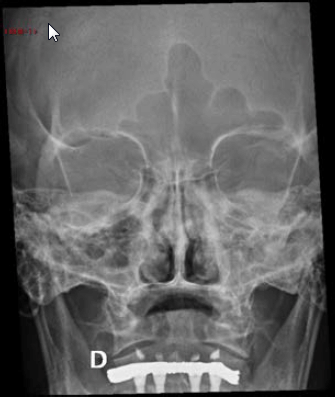

Uma paciente de 60 anos realizou radiografia de seios da face com queixa de cefaleia. Frente às imagens, considera-se que há: